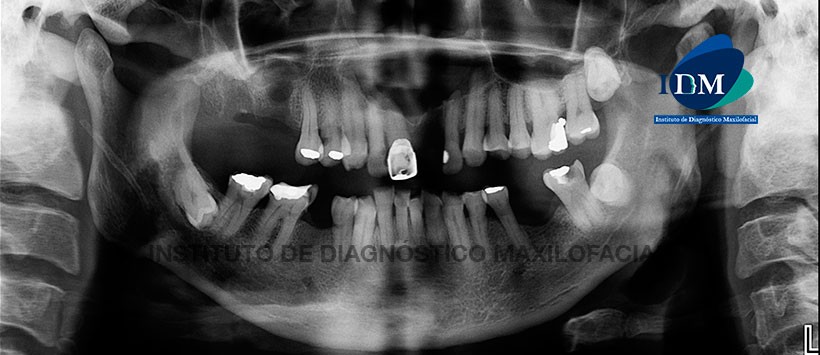

A la evaluación de la radiografía panorámica, lo más resaltante fue la presencia de una imagen radiolúcida localizada en zona anterosuperior, de límites definidos y bordes corticalizados. (Figura 1)

Posteriormente se amplió con el estudio tomográfico (Figura 2, Figura 3, Figura 4) donde se pudo evidenciar que dicha lesión tiene un tamaño de 8.3 cm3. Cabe mencionar que dicha entidad ocasiona una leve reabsorción radicular externa en la mayoría de las piezas comprometidas (12, 11, 22 y 23), borramiento del conducto nasopalatino y desplazamiento de ambas tablas óseas (a predominio de la tabla ósea vestibular).